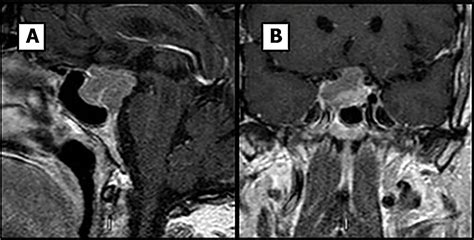

For the most accurate results, a contrast agent (often gadolinium) is frequently used. This substance is injected intravenously to highlight blood flow and differentiate between healthy gland tissue and potential lesions or tumors. The contrast agent allows the radiologist to see the pituitary anatomy in vivid detail, making it easier to spot abnormalities that might otherwise be overlooked.

In some specialized centers, advanced MRI techniques are used for a more nuanced diagnosis. For example, dynamic contrast-enhanced MRI involves taking a series of images in rapid succession immediately after the contrast is injected. This allows radiologists to see exactly how a potential tumor "fills" with blood compared to healthy tissue, offering deeper insight into the nature of the lesion. These specialized approaches are highly beneficial when standard imaging results are inconclusive but clinical suspicion of a pituitary disorder remains high.